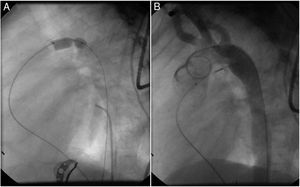

MethodsAll consecutive pediatric patients referred to our center for percutaneous PDA closure from January 2006 until September 2018 were included in this study. Medical record data was collected and reviewed retrospectively. Informed written consent was obtained from the parents or legal guardians. Indications for closure were presence of cardiac murmur, left-sided volume overload detected by non-invasive cardiac imaging, or signs of heart failure. All procedures were performed under general anesthesia. Arterial access was obtained in all patients. An intravenous bolus injection of 100 IU/kg heparin was administered at the start of the procedure. Our endocarditis prophylaxis protocol consisted of cephazolin 25-30 mg/kg every eight hours for 24 hours, and no anti-aggregation was advocated. In every patient, an aortogram was performed in the lateral projection to define the morphology and size of the duct. According to these results, feasibility for percutaneous closure was determined and, when deemed feasible, appropriate devices were selected. At our department, the Nit-Occlud® occlusion device (pfm, Cologne, Germany) has been available since 2006, with the Amplatzer™ duct occluder being implemented in 2011. As standard of care, all devices were preferably deployed anterogradely. A post-implantation aortogram was obtained to check for residual shunts or any anomaly in the device position. All patients were assessed six hours after the procedure for hemodynamic instability and unpalpable distal arterial pulses. The following day, before discharge, the location of the device was noted on a chest radiograph and a transthoracic echocardiography was performed to exclude residual leakage or other complications. Clinical and echocardiographic follow-up assessments were performed at one, three, six and twelve months after the procedure, and annually thereafter.

A coil was used in 139 patients (62.9%) and an Amplatzer duct occluder was used in 79 patients (35.7%). In the three remaining patients (1.4%), an Amplatzer vascular plug was used for closure (Figures 2-8). Despite the higher overall rate of coil device implantation, Amplatzer duct occluder usage had been clearly superior since 2011. Of all coil devices used, 55% were either 4x4 mm or 5x4 mm in size (Figure 9), and of all duct occluder devices used, 72% were Amplatzer duct occluder I 6x4 mm or 8x6 mm in size (Figure 10), which correlates to the fact that most patients who were referred had small- to moderate-sized ductus arteriosus. While ADO II and ADO II AS devices can be implanted in a retrograde fashion, only on two occasions was a retrograde deployment performed (both ADO II devices).